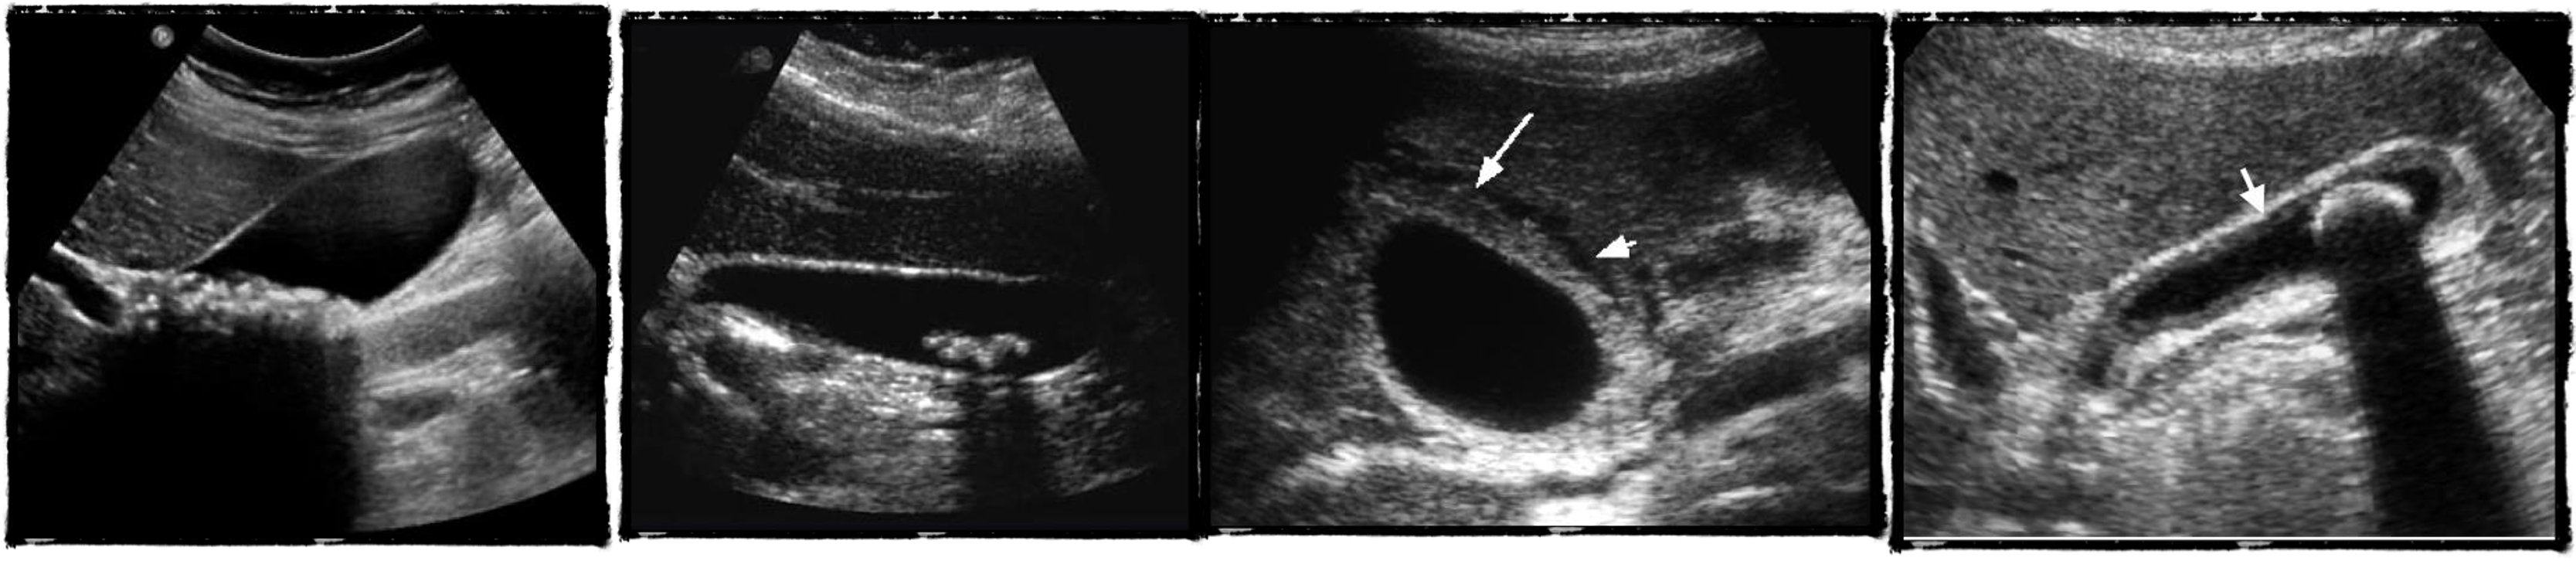

U/S

- chronic chole

- hyperechoic - post acoustic shadow…

- acute cholecystitis

- acute edematous thick gallbladder

- stone tumour

hydiatted

HCC